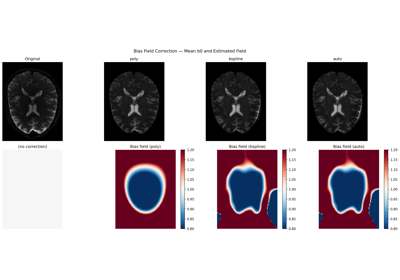

Using the free water elimination model to remove DTI free water contamination